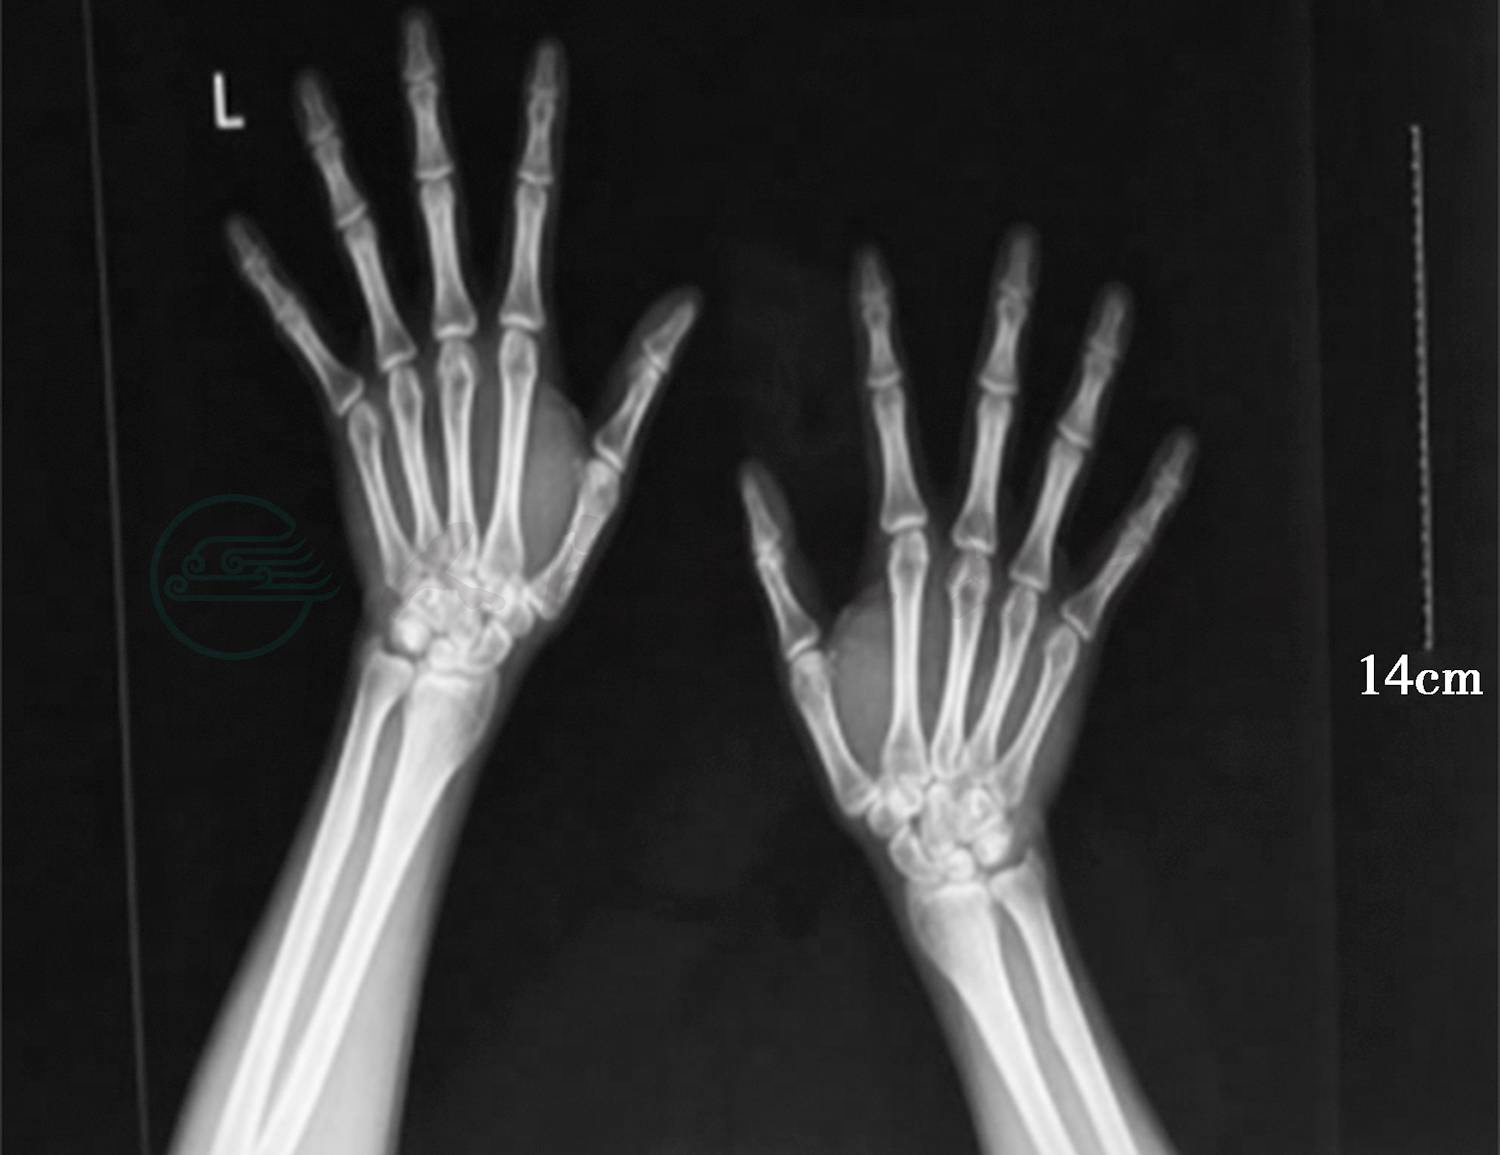

4.双手正位片(图1)未见明显异常。

图1 双手正位片